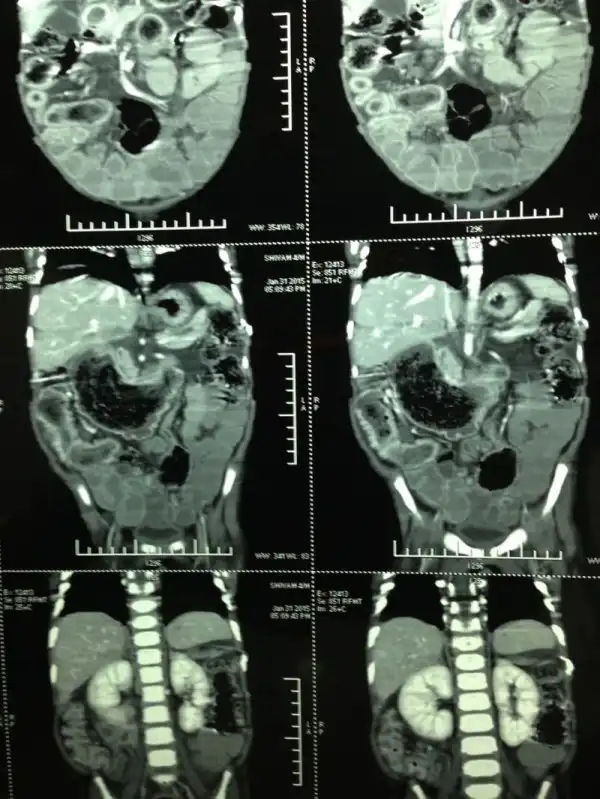

Индийский мальчуган Сивам Кумар ел собственные волосы на протяжении девяти месяцев. Это привело к тому, что он больше не смог вообще ничего съесть, так как в пищеварительном тракте образовалась пробка. В результате операции из пацана достали метровый кусок сплетенных волос. Чтобы прецедент не повторился, малого побрили налысо.